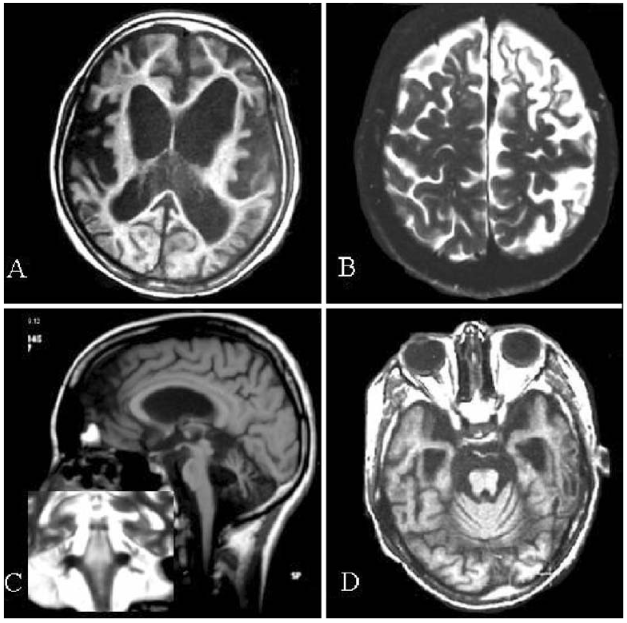

Achados típicos de doença de Wilson em ressonância nuclear magnética. A: criança de 14 anos com atrofia cortical e subcortical difusas. B: mulher de 26 anos com atrofia frontal e parietal focais à esquerda. C: moça de 15 anos com atrofia cerebelar e de tronco cerebral. D: rapaz de 16 anos com atrofia cerebelar e de tronco cerebral, com atrofia dos lobos temporais e dilatação dos ventrículos laterais (fonte)

- Ressonância magnética: parece ser sensível para detectar alterações precoces em pacientes com a doença. Mostram alterações localizadas com predileção para os gânglios da base nos casos com manifestações neurológicas. Essas anormalidades embora não sejam específicas, são altamente sugestivas. Um sinal considerado característico é o chamado “face do panda gigante” (mesencéfalo). Outra alteração recentemente descrita em pacientes com sintomas neurológicos é a presença do claustrum brilhante.